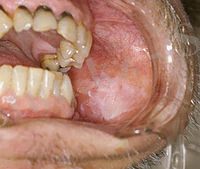

Шегрен ауру диагнозын қою үшін бірнеше әйгіленімдердің анықталуы керек. Аурудың диагностикасында міндетті түрде үш маман қызметіне жүгіну керек. Олар: окулист, стоматолог және ревматолог. Науқас ауыз қуысындағы үнемі болытын құрғақтыққа, кеуіп кетулерге, құлақ маңы бездерінде үнемі ауырсыну сезімінің болатындығына, жалпы әлсіздікке, тез шаршағыштыққа, 50-70% жағдайда үнемі болатын құлағының екі жақты ісінулеріне, тістерінің қарқынды бұзылыстарына шағымданады. Кей жағдайда бастапқы кезде көздің сулы қабықшасының кеуіп кетуіне, жарықтан қорқу сезімінің пайда болуына, көздеріне құм түскендей сезімде болатындарына шағымданады. Осымен қоса буындардағы, бұлшықеттердегі ауырсыну сезімінің болуына, астан кейін эпигастральді аймағындағы ауырлық пен дискомфорт сезімінің болуына, жүрек айнуына, тәбетінің төмендеуіне, оң жақ қабырға астында ауырлық пен ауырсыну сезіміне, аузындағы қышқылдық сезімге, майлы тамақты көтере алмауына, тамағындағы құрғақтыққа, құрғақ жөтелге және ентігуге, терісінің қызаруына т. б әйгіленімдерге шағымдануы мүмкін.

Шегрен ауруының айқын кезеңінде науқастар ауыз қуысындағы үнемі болатын құрғақтыққа, құрғақ астан кейін үнемі суды ішу керектігіне. Көбіне паротиттің асқынулары байқалады. Сілекей бездерінің ұлғаюы, температулық реакциямен, жалпы жағдайдың нашарлауымен көрінеді. Қарау кезінде құлақ маңы бездерінің ұлғаюы айқын байқалады, бездер көбіне бөлік болып көрінеді. Өршуден кейін де көлемі толығымен кішіреймейді. Ауыз қуысын қарау барысында сілемейлі қабықтың ашық-қызыл түсті, сілекей аз, сілекей көбік тәрізді немесе кілегей тәрізді болады. Үлкен сілекей бездерін басып көргенде ағындардан сілекейдің өте аз мөлшерінің бөлінетіндігін байқауға болады. Кариестің дамуын. Ауыз қуысы дисбактериозының айқын көріністерін, жиі кездесетіні стоматит (саңырау құлақтық, вирустық, травмалық) . Сиалометрия кезінде секреция төмендеуінің екінше кезеңі анықталады, сілекейде қабынулық бөлшектер табылады.